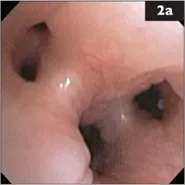

2 A 13-year-old neutered male Shih Tzu has been coughing for the past 3 weeks, after he was at a boarding facility for several weeks. Decreased appetite and weight loss were noted recently. Amoxicillin with clavulanate and hydrocodone were prescribed elsewhere for suspected bronchitis, but the owner has had trouble administering the medication. The dog is quiet, but alert and responsive. Body temperature, HR, and respiratory rate are normal. Soft pulmonary crackles are heard over the left hemithorax. Tracheal palpation elicits a non-productive cough. The rest of the physical examination is normal. Chest radiographs show a moderate to severe bronchointerstitial pattern in the caudal lung with alveolar infiltrates in the right cranial lobe. Cardiac size and pulmonary vasculature are normal. A hemogram shows mild thrombocytosis, but is otherwise normal; serum chemistries and urinalysis are unremarkable. Bronchoscopy (2a, b) and BAL are performed.

i. What findings are shown in the bronchoscopic images?

2 i. The airways appear diffusely edematous with mild erythema consistent with generalized bronchial inflammation. Small yellowish tan nodules are seen on some surfaces (2b, from right cranial bronchus).

ii. The radiographic pattern suggests pneumonia or an infiltrative inflammatory or neoplastic disease. Given the history of boarding, infectious tracheobronchitis with secondary pneumonia is a consideration. Small nodules within the airways most often result from chronic inflammation and mucosal proliferation secondary to chronic bronchitis, but neoplastic infiltration is another consideration. Nodules found only near the carina may signal infection with the parasite Oslerus osleri in endemic areas. This dog’s systemic signs, along with the relatively recent onset of coughing, are not typical for chronic bronchitis.

iii. In addition to BAL cytologic analysis and culture, airway brushings and pinch biopsy of a nodule should be obtained during the bronchoscopic procedure. If evaluation of these samples does not yield a definitive diagnosis, lung biopsy is recommended. In this dog, cytologic evaluation revealed mild purulent inflammation, mild chronic hemorrhage, and variably-sized cohesive clusters of highly vacuolated cells thought to be carcinoma cells. BAL cultures yielded no aerobic or anaerobic growth.